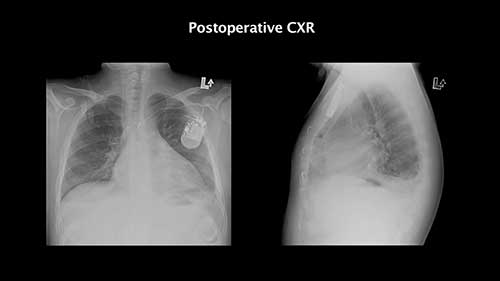

孟买血型患者心脏手术